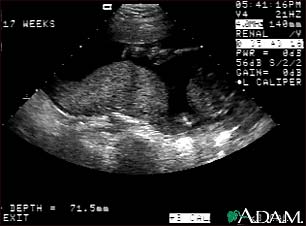

Ultrasound, normal placenta - Braxton Hicks

This is a normal ultrasound performed at 17 weeks gestation. It shows the placenta during a normal (Braxton Hicks) contraction. Throughout the pregnancy, the uterus periodically contracts to facilitate better blood flow through the placenta and the fetus. In this ultrasound, the placenta can be seen as the mound-shaped object in the middle of the screen. At the bottom of the image, the mother's vertebra can be seen as a round object. When the uterus is not contracting, the placenta would appear much flatter.